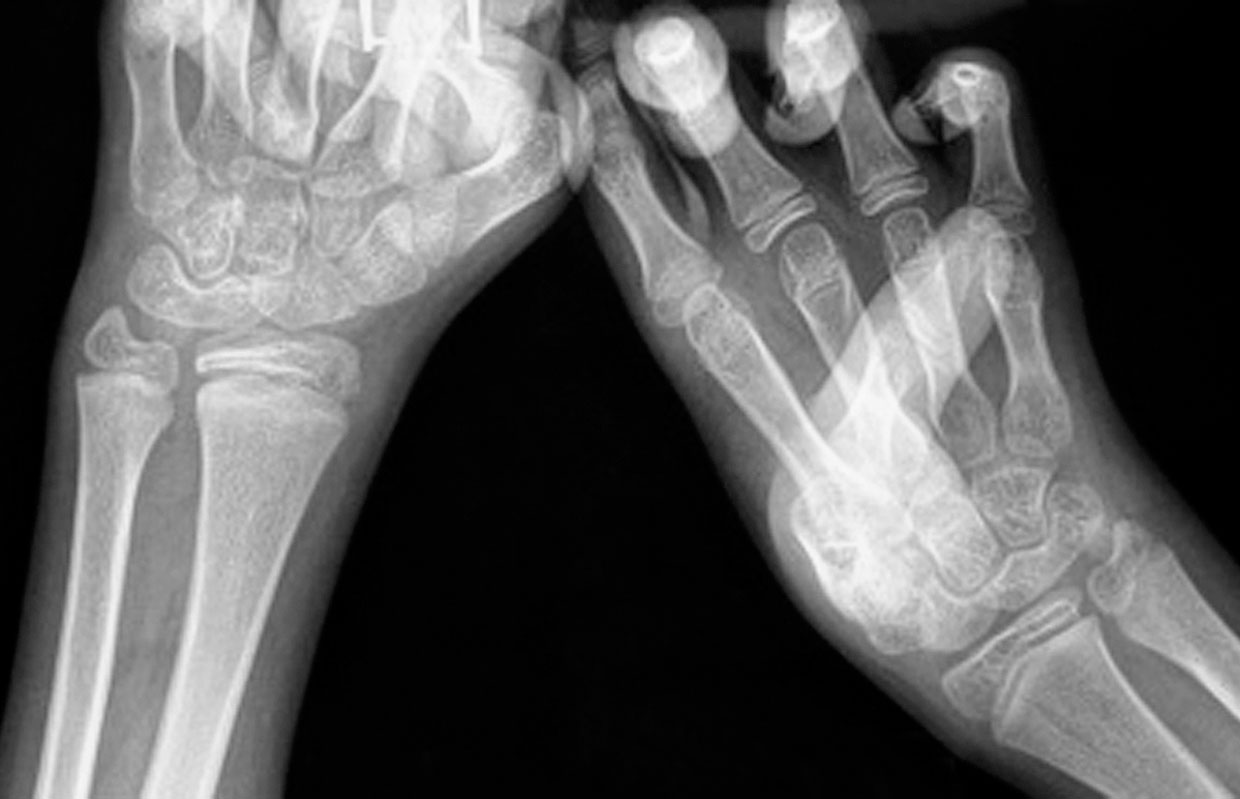

图1-2-29 指间关节融合

图1-2-30 指间关节融合X 线片

先天性双手指间、掌指关节纤维性(或软骨融合)融合